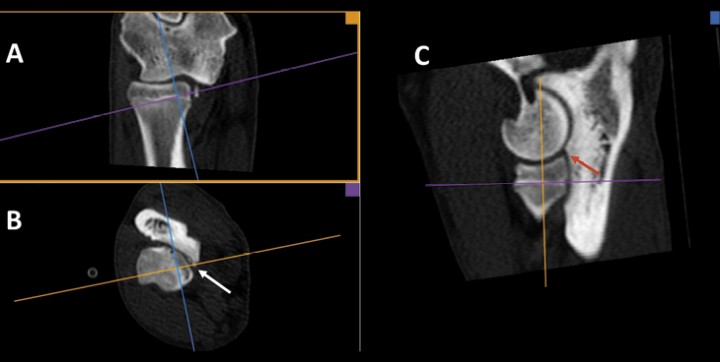

<p>Pastor Alemán macho de 9 meses. Planos dorsal (<strong>A</strong>), transversal (<strong>B</strong>) y sagital (<strong>C</strong>). Reconstrucción 3D MPR multiplanar para conseguir planos oblicuos. Con este tipo de reconstrucción cada eje tiene un color y produce la imagen en el recuadro del color correspondiente. Existe una fragmentación de la apófisis coronoides medial del cúbito (flecha blanca). En B se ha orientado la línea azul para conseguir el plano sagital perpendicular a la apófisis coronoides (C). En el plano sagital se aprecia un marcado escalón (de 2,6 mm) entre la apófisis coronoides lateral y la epífisis proximal del radio (flecha roja) lo que indica que existe una incongruencia articular.</p>

Pastor Alemán macho de 9 meses. Planos dorsal (A), transversal (B) y sagital (C). Reconstrucción 3D MPR multiplanar para conseguir planos oblicuos. Con este tipo de reconstrucción cada eje tiene un color y produce la imagen en el recuadro del color correspondiente. Existe una fragmentación de la apófisis coronoides medial del cúbito (flecha blanca). En B se ha orientado la línea azul para conseguir el plano sagital perpendicular a la apófisis coronoides (C). En el plano sagital se aprecia un marcado escalón (de 2,6 mm) entre la apófisis coronoides lateral y la epífisis proximal del radio (flecha roja) lo que indica que existe una incongruencia articular.

Solamente hemos encontrado IA en el 28% de los codos. La coexistencia de EACM con IA ya ha sido señalada.[ Samoy Y, Gielen I, van Caelenberg A. et al. Computed tomography findings in 32 joints affected with severe elbow incongruity and fragmented medial coronoid process. Vet Surg 2012; 41: 486-494. [PubMed] ] Aunque la radiografía cuenta con una sensibilidad razonable una vez que la distancia, en el plano sagital, entre la apófisis lateral del cúbito y la epífisis proximal del radio es mayor de 2 mm,[ Alves-Pimenta S, Colaço B, Fernandes A et al. Radiographic assessment of humeroulnar congruity in a medium and a large breed of dog. Vet Radiol Ultras 2017; 58: 627-633. [PubMed] ] la TC resulta mucho más precisa que la radiografía a la hora de valorar dicha IA. Para ello, habitualmente realizamos una reconstrucción multiplanar en 3D, orientando la imagen en planos oblicuos a la apófisis coronoides, obteniendo así la medida radiocubital más exacta.[ Lau SF, Woorhout G. Dog positioning for CT scanning of the elbow joints. Proc. 29th Ann Meet Intern Elbow Working Group, Bangkok (Thailand) 2015; 23-24. , Wisner E, Zwingenberger A. (2015). Atlas of Small Animal CT and MRI. Wiley-Blackwell, West Sussex (UK): 617-635. , Holsworth IG, Wisner ER, Scherrer WE et al. Accuracy of computerized tomographic evaluation of canine radio-ulnar incongruence in vitro. Vet Surgery. 2005; 34: 108-113. [PubMed] , Novales-Durán M, Lucena-Solís R, Tovar-Escriche M, Hernández-Robles E, Ginel-Pérez P, Blanco-Navas B. Claves para interpretar y comprender la tomografía computarizada del codo normal del perro. Clin Vet Peq Anim 2020; 40: 131-139. ] El plano sagital permite apreciar el escalonamiento entre la apófisis lateral del cúbito y la epífisis proximal del radio, mientras que el plano dorsal posibilita valorar la asimetría humerorradial.